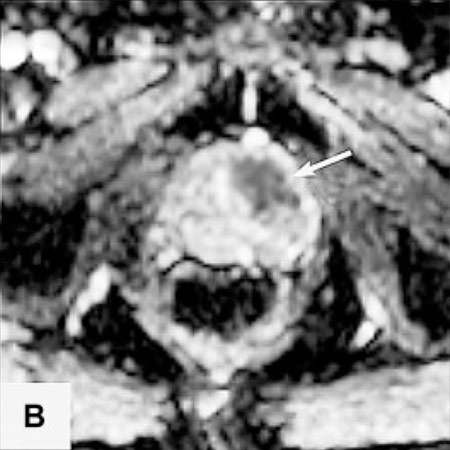

Die Probleme der Fusionsbiopsie und der Unsichtbarkeit von Krebsherden im Ultraschall lassen sich auf elegante Weise vermeiden, wenn die Biopsie direkt MRT-gesteuert im Kernspintomographen selbst ausgeführt wird.

In der Vitus Privatklinik nutzen wir diese Möglichkeit der präzisen, direkt durch MRT-Bilder gesteuerten Biopsie. Dazu wird die Biopsienadel entweder manuell oder mit einem Soteria Biopsie-Roboter in den verdächtigen Herd gesteuert, unter direkter MRT-Kontrolle. Dies ermöglicht es, mit hoher Präzision, die Biopsienadel direkt in den verdächtigen Herd in der Prostata zu steuern. Dort angekommen kann die Biopsie im MRT direkt verfolgt werden, und nach der Probenentnahme durch die Darstellung des Stichkanales überprüft werden, ob der Herd getroffen wurde. Auf diese Weise können auch kleine Karzinomherde mit hoher Sicherheit biopsiert werden2.